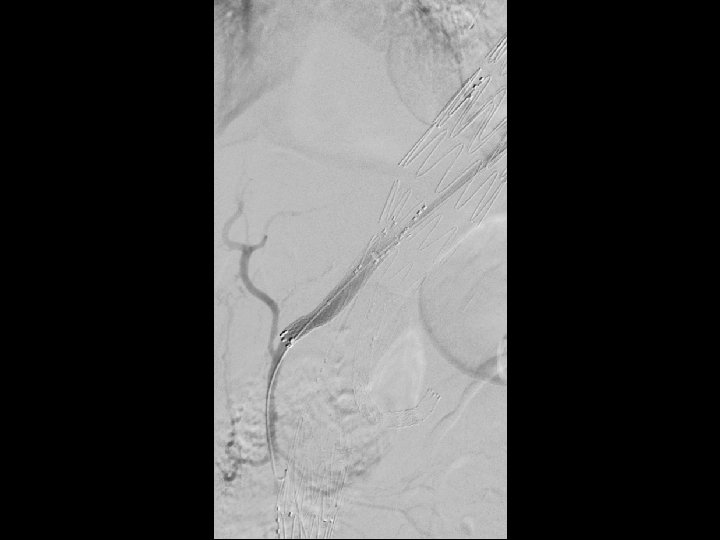

Technique • Initially the left subclavian was bypassed and plugged. • Two Cook TX 2 TAA endografts were placed, the first covering the occluded left SCA. • Segment three was a Cook Zenith endograft with branches for the celiac, SMA, and left renal artery. • Segment four was a customized fenestrated bifurcated endograft. • The IMA was chronically occluded. • Atrium stent for the fenestrated component and self expandable stents for branched segments. • Procedure was staged to prevent spinal cord ischemia, the SMA branch was sealed 2 weeks after initial endovascular procedure.